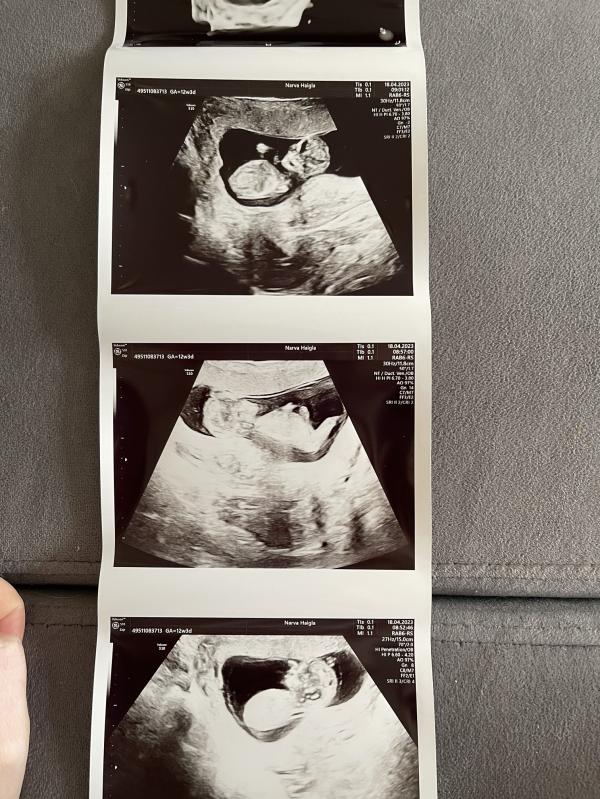

Мы тоже были сегодня на узи🥰

Развиваемся хорошо,все прекрасно работает,токсикоз пока еще есть.

Пдр-28 октября🌸